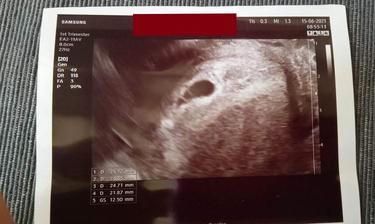

Druhé štěstí 💖 Únorová Klárka 💖